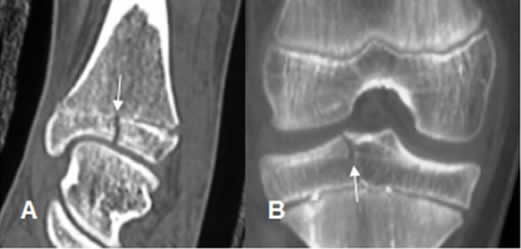

Fig 75. Salter tipo III.

A: TAC reconstrucción sagital y B: TAC reconstrucción coronal. Fracturas verticales en las epífisis de la tibia, por lesiones tipo III.